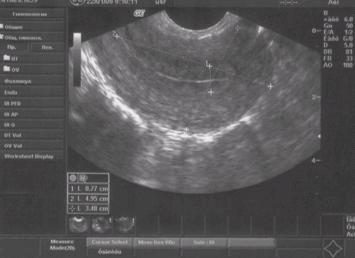

Ультразвук это эффективная и едва ли не единственная мера исследования женской репродуктивной системы. А все, потому что методика безопасна и не оказывает влияния на репродуктивные органы. При помощи УЗД есть возможность оценить состояние, структуры, расположение и форму всех органов малого таза. О обследовании таких органов как яичники или маточные трубы, да и сама матка знают многие дамы, а вот что такое процедура М-эхо понимает мало кто. Тем не менее, она используется довольно часто.